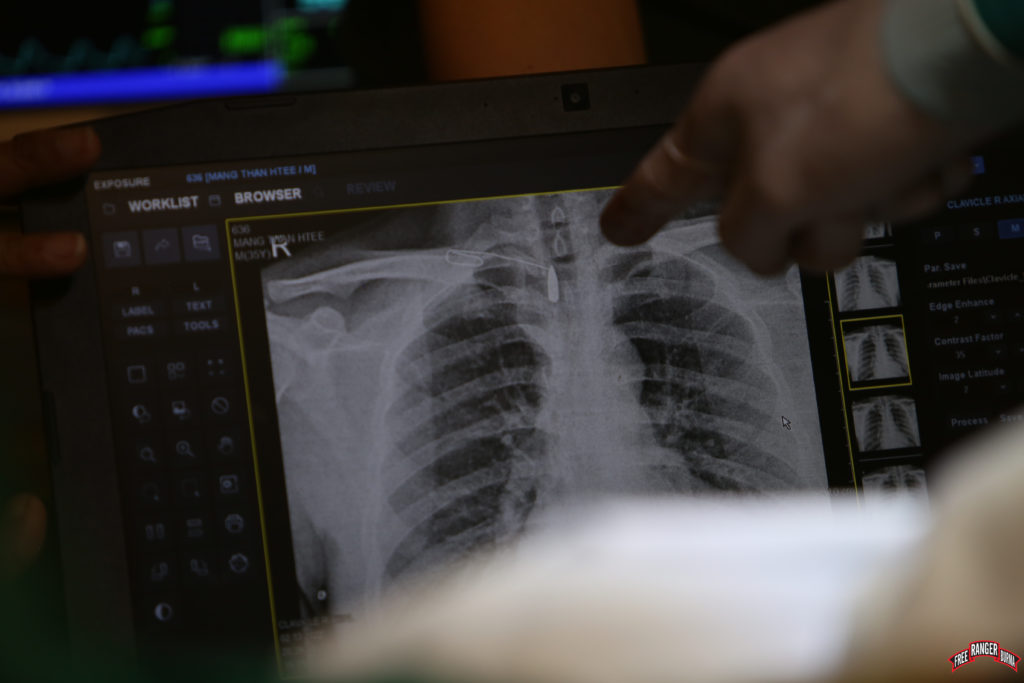

As the patient shared his story, we learned that he had been ambushed by the Burma Army and as he fled, was shot at close range with an assault rifle. I found his story hard to believe. A round fired in such close proximity would have gone through him, leaving him long dead or at least paralyzed. To our surprise when we viewed his xray, we could see a clear bullet lodged in his back. “Should I take it out?” I wondered. I had learned over the years that many war wounds with retained foreign bodies like this actually do not need to come out. As strange as it may seem, thousands of people live a healthy life while carrying bits of metal in them - their only disadvantage being unable to get through airport security without setting an alarm off.

The next challenge was to accurately find the location of the bullet. The military has a term called “field expediency,” also known in humanitarian jargon as “frugal innovation.” What these terms essentially mean is improvising or re-engineering something for a different purpose. Locating a bullet in a 3D patient with an x-ray that gives you a 2D film is not easy. Using serial xrays and a strong paperclip taped to the patient’s back, I was able to locate the exact position of the bullet. Even during the operation it took much effort to find the bullet, but alas, it was lodged by the facet joints of his spine. That the bullet did not kill him or leave him paralyzed is, again, a miracle to me. The bullet also showed no signs of ricochet as it was still perfectly formed.